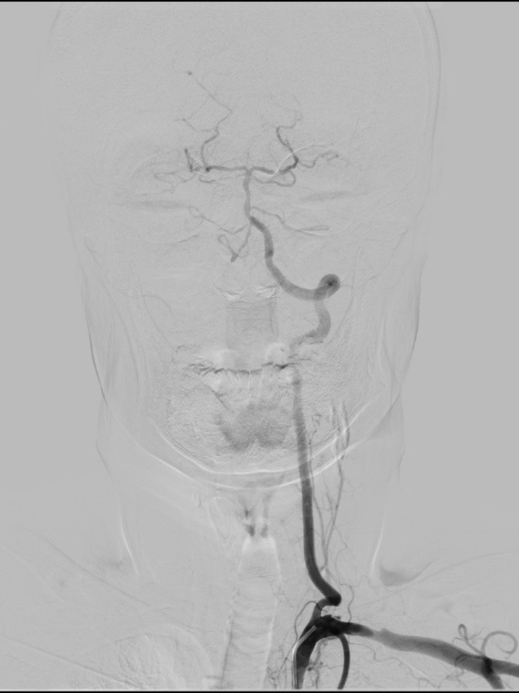

桡动脉入路行DSA:右侧颈内动脉C1段重度狭窄。

右侧桡动脉穿刺,置入7F薄壁鞘,造影示右侧颈内动脉C1段重度狭窄,狭窄率约90%,狭窄长度约22mm。通过加硬泥鳅导丝、125cm SIM2造影导管辅助,将5.5F Introsky X导管鞘置于右侧颈总动脉远端,选择KangFly微导丝携带Spider FX保护伞通过狭窄病变后释放保护伞,5.0*30mm球囊预扩张,置入9*40mm自膨式支架。

术后即刻影像:造影见右侧颈内动脉C1段血流通畅,mTICI3级。